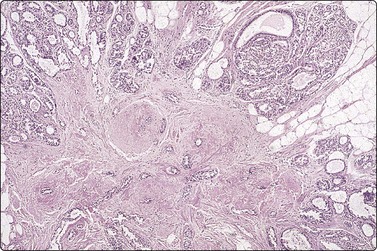

image image

Fig. 7.15 Regenerative epithelial atypia in mastitis

(A) Atypical, reactive/regenerating epithelial cells with a background of histiocytes, inflammatory cells and debris (MGG, HP); (B) Corresponding tissue section (H&E, IP).

Problems and differential diagnosis

Regenerative atypia of duct epithelium in an area of mastitis can look worrying and suspicious (Figs 7.15A and 7.17). In addition, the nuclei of reactive histiocytes may appear large and atypical, particularly in air-dried smears. False-positive diagnoses in cases of chronic mastitis and organizing fat necrosis have been reported. However, large numbers of both acute and chronic inflammatory cells are rarely seen in carcinoma. In medullary carcinoma with lymphocytic infiltration and in comedocarcinoma, in which lymphocytes and histiocytes are mixed with the carcinoma cells, the latter dominate and nuclear morphology is obviously malignant. The presence of necrotic cell debris should evoke a suspicion of malignancy.